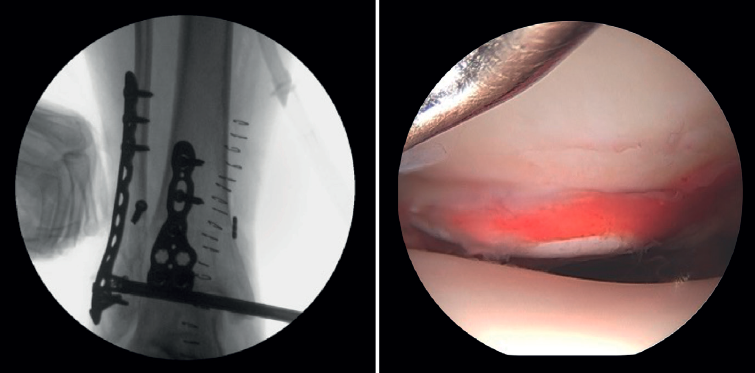

- Valoración de la reducción del maléolo posterior: con la artroscopia podemos verificar la reducción del maléolo posterior(5) (Figura 2).

Lee describe una técnica novedosa que utiliza una guía de broca con la artroscopia de tobillo para la reducción de fragmentos articulares en fracturas del maléolo posterior. En particular, esta técnica es beneficiosa para pacientes con fracturas trimaleolares que presentan un fragmento articular deprimido, ya que permite una reducción anatómica y minimiza la necesidad de incisiones extensas(11). - Extracción de cuerpos libres. La presencia de cuerpos libres dentro de la articulación es un hallazgo común en las fracturas de tobillo. El 33% de los pacientes con artroscopia presentaron cuerpos sueltos intraarticulares retirados durante la intervención (24 de 71 casos)(12). La artroscopia permite la eliminación precisa de los cuerpos libres intraarticulares, los cuales pueden producir dolor, bloqueo o limitación de la movilidad y daño del cartílago articular(13).

La artroscopia asiste a la RAFI para evaluar la congruencia de la superficie articular. Es especialmente útil para la reducción del maléolo medial. La tasa de mal reducción en fracturas del maléolo medial es del 22,2 al 32,6%(15,16). La artroscopia inicial permite valorar si la reducción del maléolo tibial puede realizarse de forma abierta o cerrada. En casos con desplazamiento significativo, se opta por una síntesis abierta, manteniendo siempre control artroscópico durante el procedimiento para asegurar una reducción precisa y evitar la rotación del fragmento distal (Figura 4).